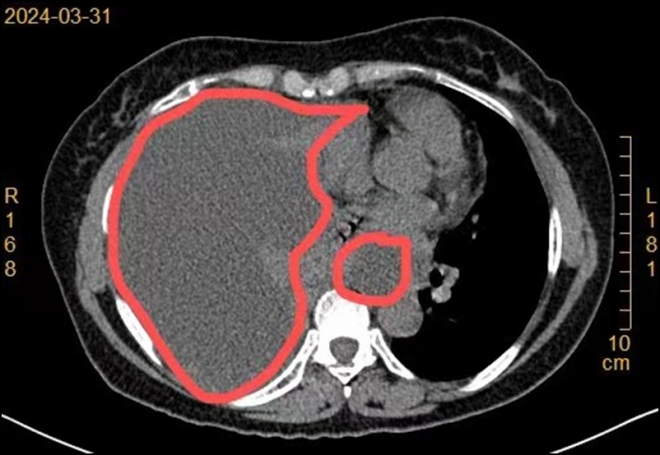

中国网络资讯台4月10日讯 近半个月来,60岁的陈阿姨(化名)一直被咳嗽、气短、全身乏力和食欲不振所困扰,于是前往苏州九龙医院呼吸科门诊就诊。接诊的主任医师王军通过胸部CT检查,意外地发现了陈阿姨右侧存在大量胸腔积水,便安排她住院治疗。同时,呼吸内科也专门为此组织了一场专家讨论会。专家们一致认为应尽快为患者安排内科胸腔镜检查,以便更准确地诊断病因。

术中,采用“清醒镇静+局部麻醉”的方式,通过1cm小切口置入鞘管。内科胸腔镜进入胸腔后,发现胸腔内大量血性胸腔积液,壁层及脏层胸膜多发菜花状增生物。予以抽吸胸水后,用活检钳多部位夹取病变组织送检,进而为患者明确病因。